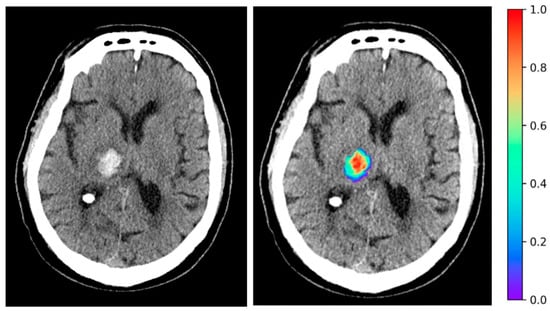

2.2. ICH Segmentation and Extraction of Radiomic Features